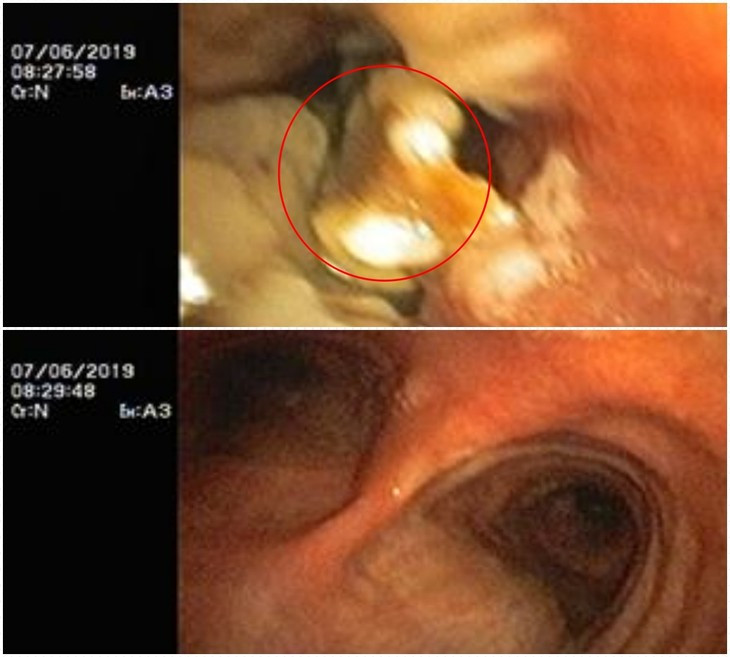

Kết quả chụp cắt lớp lồng ngực cho thấy hình ảnh dị vật sắc nhọn ở vị trí phế quản đáy trái. Bệnh nhân được chỉ định nội soi phế quản cấp cứu lấy dị vật.

Kíp bác sĩ khoa Hô hấp và Bệnh nghề nghiệp đã tiến hành nội soi phế quản dưới gây mê và gắp thành công dị vật là 1 chiếc đinh vít dài khoảng 1 cm có đầu sắc nhọn.

Quá trình nội soi người bệnh được thực hiện gây mê nên dù dị vật nằm khá sâu trong phế quản tuy nhiên bác sĩ đã thao tác lấy ra dễ dàng, không gây cảm thấy khó chịu cho người bệnh. Sau thủ thuật, bệnh nhân hết các triệu chứng ho, đau ngực, khó thở. Bệnh nhân ổn định và được xuất viện sau 1 ngày.

Mảnh xương cá trong phế quản bệnh nhân gần 3 tháng đã được gắp ra.